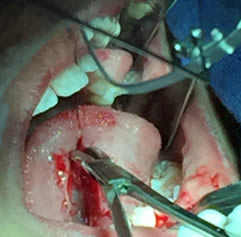

• Se eliminó el frenillo en su totalidad  con la ayuda de tijeras iris recta y hoja de bisturí del No. 15 así como todo el tejido residual fibroso correspondiente al frenillo. Se realizó genioplastia con pinza de mosco y disección roma para liberar adecuadamente la inserción frénica hasta la cara lingual de los incisivos inferiores. (Figuras  7, 8 y 9)

Figuras 7 y 8. Eliminación total del frenillo y genioplastia